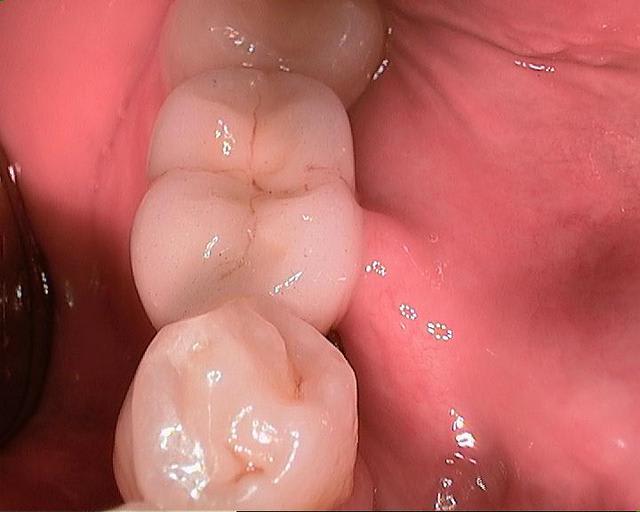

- Trés vite on ne fait pratiquement plus que du flapless, les forets coniques permettant d'attaquer des crètes en pente facilement.

- Invasivité moindre, tout cela a déja été dit mais surtout une autre gestion du temps vu la rapidité de pose. Par exemple, la semaine dernière, extraction de racine 13, 10minutes, pose de 14x3.5, 5 minutes (un seul foret, pas de biomat, pas de tech biocol, la gingiva-clix sert de membrane).

- Le Evolution (2 pièces connection conique) conduit inéluctablement au Vierkant ( une pièce) tant ce dernier, avec l'usage des Prep-Caps zircone, est agréable, prothèse sans vis. Les gros poseurs sur le forum Champions utilisent surtout le Vierkant.

-Peu de suites opératoires, évidemment.

-Necessité de changer les habitudes, forage lent, à 200T/mn, éventuellement sans irrigation, contrôle de cavité obligatoire, contrôle de couple.

-Dans les rares cas en chirurgie à lambeau (voir photo fin), on se rend compte qu'on a perdu la main, six mois sans décoller..